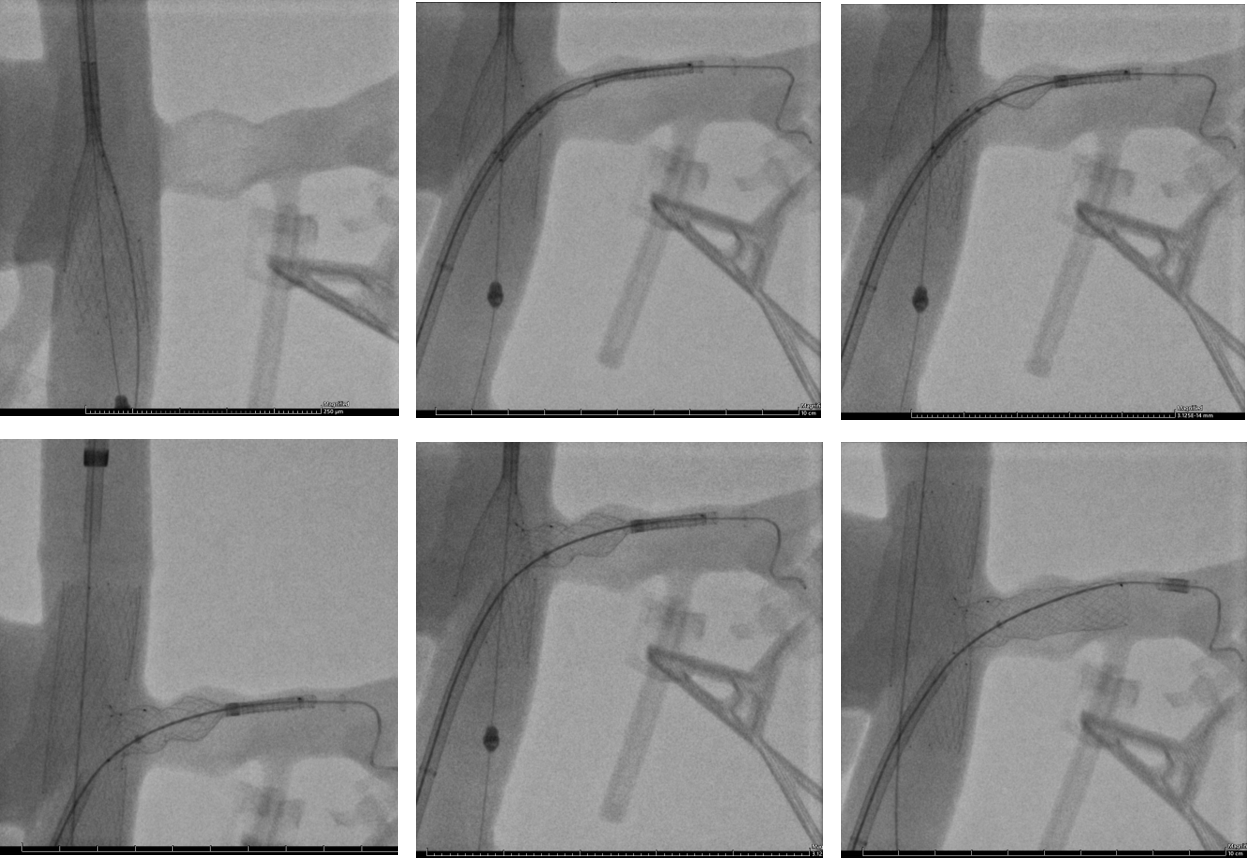

PRINCIPE DE FONCTIONNEMENT

Le T-Stent veineux a été conçu pour restaurer le flux sanguin dans la veine rénale comprimée, cœur du Nutcracker Syndrome. Grâce à son architecture modulaire et à ses connexions élastiques, il s’adapte à la morphologie de la veine tout en absorbant les mouvements naturels de l’abdomen. Une fois positionné dans la zone de compression, il crée un canal stable et homogène qui empêche l’écrasement de la veine par les structures environnantes.

Cette stabilité mécanique permet de réduire la pression intraveineuse, de rétablir une circulation fluide et de soulager durablement les symptômes, sans provoquer de protrusion ou de surdilatation.

Les équipes d’ID NEST collaborent avec plusieurs centres hospitaliers universitaires européens afin d’évaluer la performance du T-Stent sur le long terme.

Des études cliniques multicentriques sont en préparation pour mesurer les résultats fonctionnels, la durabilité du dispositif et l’amélioration de la qualité de vie des patients.